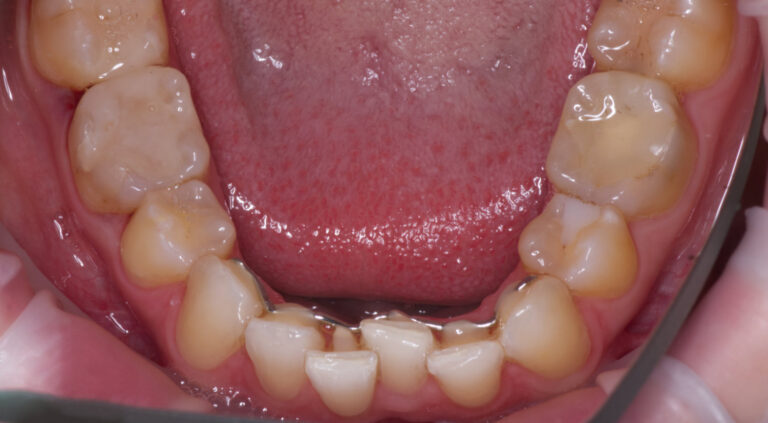

Kieferorthopädie, Zahnspange

5 Monate

Von Behandlungsbeginn bis Ende.

Nachher

Retainer unsichtbar verklebt, um das Behandlungsergebnis dauerhaft zu halten.